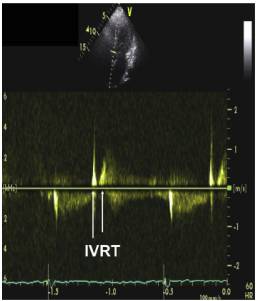

5、HFpEF—左室舒张功能评估指标

6、多普勒超声指标正常值范围

7、HFpEF—左室舒张功能指标参考值范围

8、二尖瓣口舒张期血流频谱指标1

●Valsalva 动作E/A比值 (1.3—0.6):E/A比值减少≥50%对提示LV充盈压增高具有高度特异性,但是变化幅度较小并不提示舒张功能正常。

●当二尖瓣口血流及二尖瓣环速度测量仍不能确定病人的舒张功能时,Valsava动作还是可以作为一种保留的检查手段。

9、二尖瓣口舒张期血流频谱指标2

10、二尖瓣环运动速度指标

左室舒张功能受损

①室间隔侧e’< 7 cm/s;

②侧壁侧e’< 10 cm/s;

③平均E/e’> 14